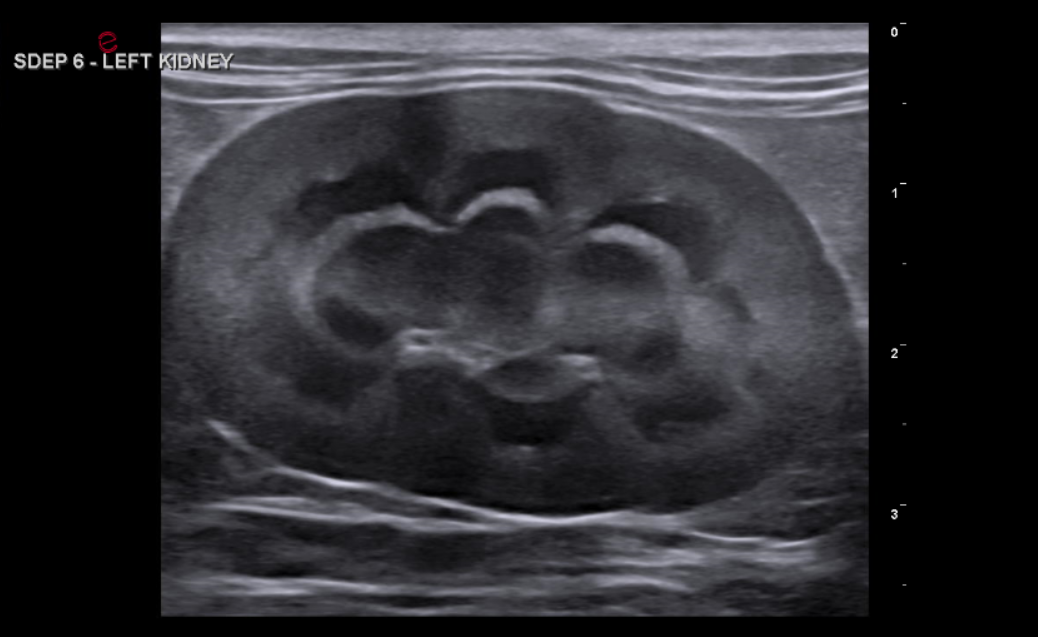

abdominal ultrasound

Complete abdominal ultrasound captures detailed videos and images of internal organs to aid in the diagnosis of various conditions and help guide treatment decisions.

Organs interrogated include liver, gallbladder, pancreas, adrenal glands, kidneys, bladder, spleen, colon, stomach, small intestines, lymph nodes, vessels, +/- reproductive organs.